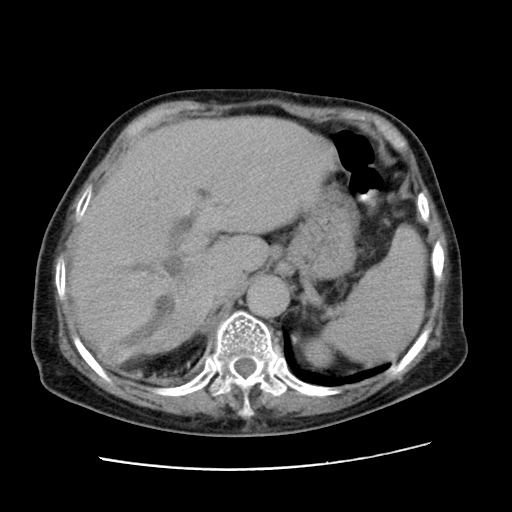

女,77.无不适

肝脏变异、异位胆囊,肝右叶肝内胆管结石并肝内胆管扩张。

肝右叶肝内胆管结石并肝内胆管扩张。

肝右叶肝内胆管结石并肝内胆管扩张

胆总管扩张

肝右叶肝内胆管结石并肝内胆管扩张。胆总管下段梗阻,考虑壶腹部占位。

右侧肝内胆管局限性扩张,其内密度不均匀,扩张的胆管壁增厚,考虑肝内胆管炎合并结石可能性大